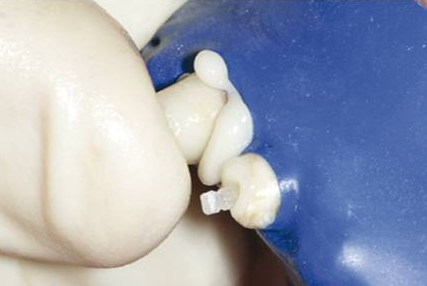

-將調(diào)好的材料充入核成型罩,扣在樁上,保證材料與肩臺緊密粘接。光照20秒初步固化。去掉多余的樹脂水門汀,再繼續(xù)光照直至固化。如不用光照,其化學(xué)固化的時間從調(diào)和開始約為8分鐘;也可用用冠核材料直接堆核,進行冠核的修復(fù)

-用光固化燈從不同側(cè)面將冠核樹脂材料照透

-核材料完全固化后,去掉核成型罩,修整冠核形態(tài)